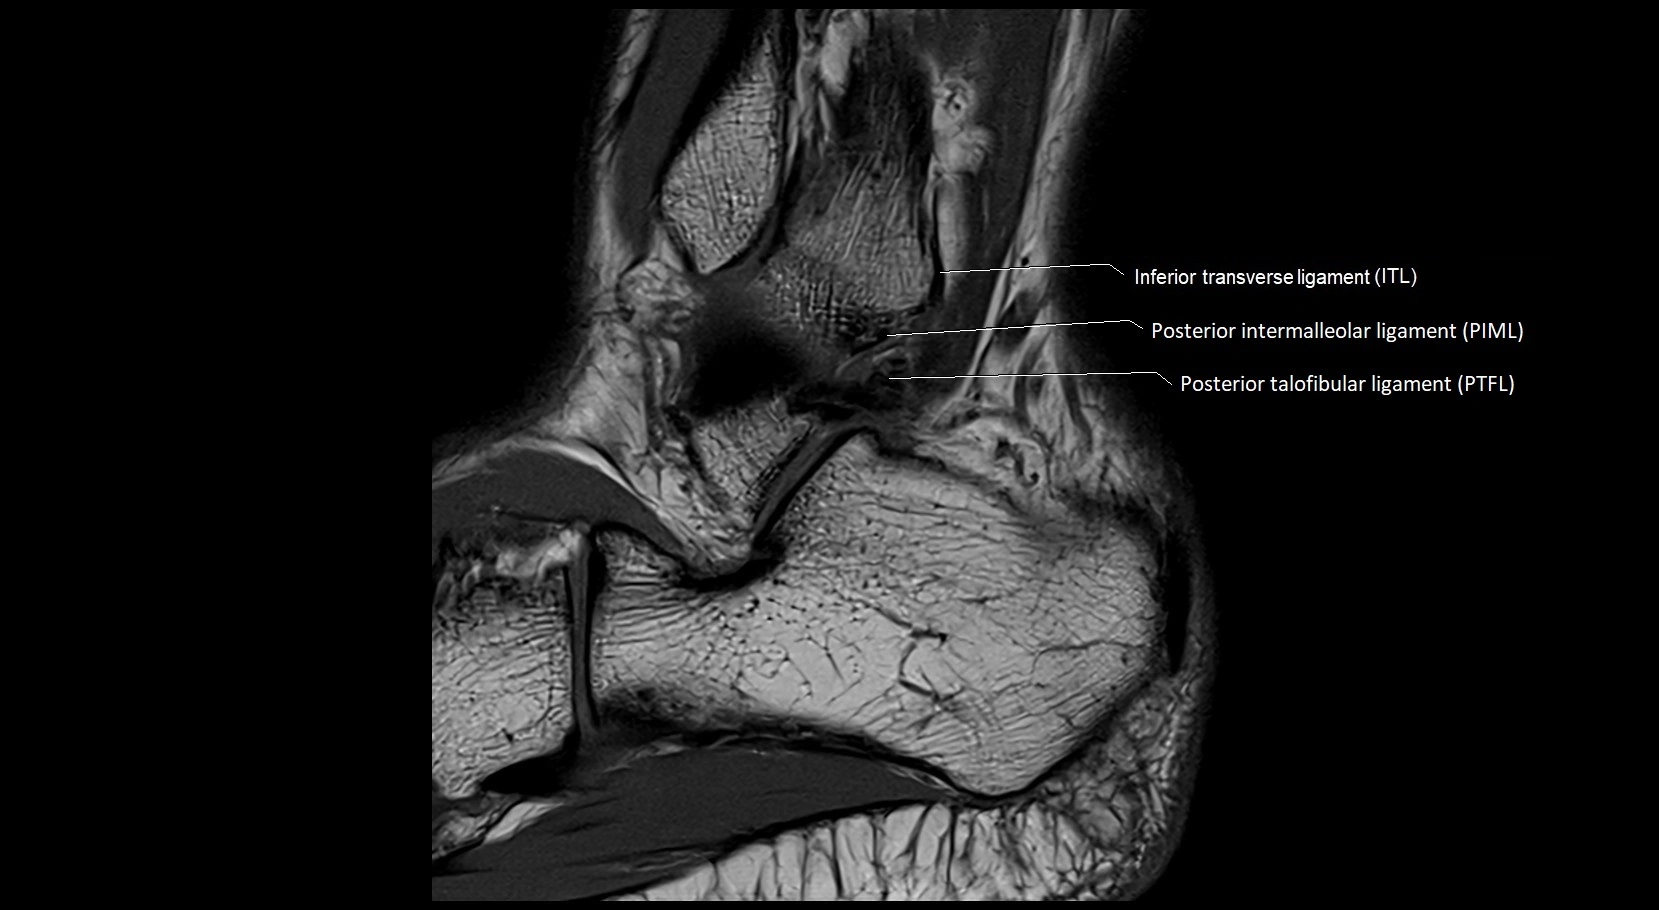

MRI image

image